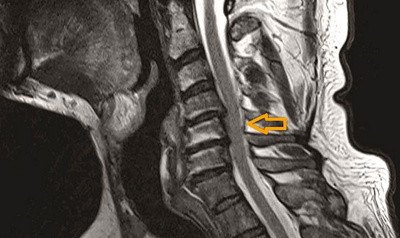

Abb. 2

MRI-Aufnahme des Patienten nach der Operation. Der Spinalkanal wurde von hinten erweitert, das Rückenmark hat nun wieder genügend Platz (siehe Pfeil). Die vor der Operation bestehenden Schmerzen, Missempfindungen und Kraftlosigkeit in den vier Extremitäten haben sich nach dieser Operation vollständig erholt.